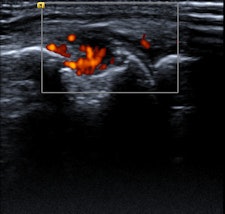

In the 12-page article, the authors outline the role of imaging -- in particular radiography, MRI, CT, ultrasound, and nuclear medicine-- for the diagnosis and monitoring of rheumatological disorders, concentrating on rheumatoid arthritis, inflammatory spondylarthropathies, and gout.

Radiographs might show evidence of bone erosion and/or other reactive bone change with ankylosis of the spine, the most extreme form of reactive bone change, according to Tins and Butler. While it is important to note these findings and suggest the diagnosis if unsuspected, radiographs are of limited value in the diagnosis of early inflammatory spondyloarthropathy because of the high false-negative rate. To an even greater extent than in rheumatoid arthritis, the radiographic changes often lag behind the clinical presentation by years, they pointed out.

"Nevertheless, rheumatologists in the U.K. often request plain x-rays because the current U.K. NICE (National Institute for Health and Care Excellence) criteria for the use of TNF (tumor necrosis factor) inhibitors in ankylosing spondylitis require that the patient fulfills the modified New York radiographic criteria. While CT is more sensitive for reactive bone change, it is insensitive for edema-like change of bone marrow or soft tissues and MRI is preferred for this," they stated.